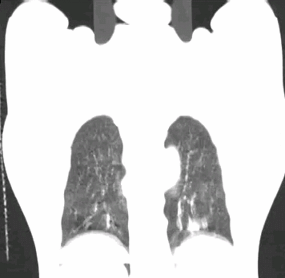

病例资料:男性,62岁,左下肺转移肿瘤。 扫描方法: 常规CT平扫

临床价值:使用4D-CT扫描可以准确评价肿瘤运动范围,确定肿瘤ITV(内靶区)。

使用D4D呼吸门控扫描,可清楚观察到肿瘤本身随呼吸周期运动的情况。

使用A4D软件测量,肿瘤随呼吸周期的运动幅度近24mm。

扫描结束之后,使用Advantage 4D软件可把图像分成10个呼吸期相,生成MIP图、AveIP图和minIP图。使用Advantage SIM MD软件可以在4D运动的图像上实时勾画和修改靶区,确定肿瘤ITV,比过去凭经验外扩范围的方式,可更精确的确定肿瘤放射治疗的范围。此外,在Advantage SIM MD上勾画的靶区文件为RT DICOM格式,可以发送给TPS(放疗计划系统),TPS不仅可以读取,如有需要还可进行编辑。